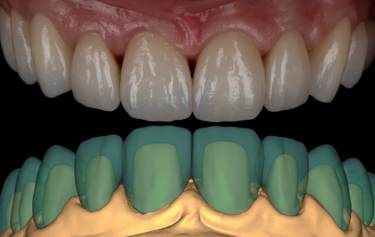

Figure 4: Digital mock-up for additive composite bonding

Figure 5: SmileFast stent placement

Figure 6: Direct comparison of digital mock-up and actual composite transfer

After full consultation and discussing all the options, costs, timeframes, on-going maintenance and repair costs, the patient proceeded to explore her options. A full set of clinical photos and digital intra-oral scan of her dentition was submitted to SmileFast where a digital mock-up for a restorative solution was returned (Fig. 4). Using the SmileFast integrated 3D software allowed her to visualise and understand the proposed option to correct and rebuild every tooth back to the correct proportions.

Figure 14: Final full mouth digital restoration designs

Digital scans were sent to the laboratory via 3Shape Trios intraoral scanner along with photos and instructions for the planned smile aesthetics. The scans were then imported into Exocad CAD design software and an upper and lower diagnostic digital mock-up was produced to create the best “first draft” of the expected outcome. The models were printed, and silicone indexes of the models made so that the diagnostic design could be transferred accurately to the mouth.

On receiving the scans of the final tooth preparations, the laboratory was able to overlay the planned final restorations which the milled temporaries had been based upon. The small modifications to the occlusion which was completed at the earlier temporary stage could be adapted into the digital design, and then the individual restorations adapted to the refined finishing margins of the final tooth preparations (Fig. 14). The final restorations were then milled in IPS e.max ZirCAD Prime Esthetic in the lighter BL4 shade using the PrograMill PM7 milling unit. New working models were 3D-printed of the preparations, and a second set of oversized models were made to compensate for the increased size of the pre-sintered Zirconia (Fig.15). The larger model was scaled up to match the shrinkage factor of the zirconia to allow the restorations to be checked on the oversized model. This additional check stage allows for assessment of marginal fit and contact areas, in addition to checking the passivity of fit and the occlusion, ahead of sintering.